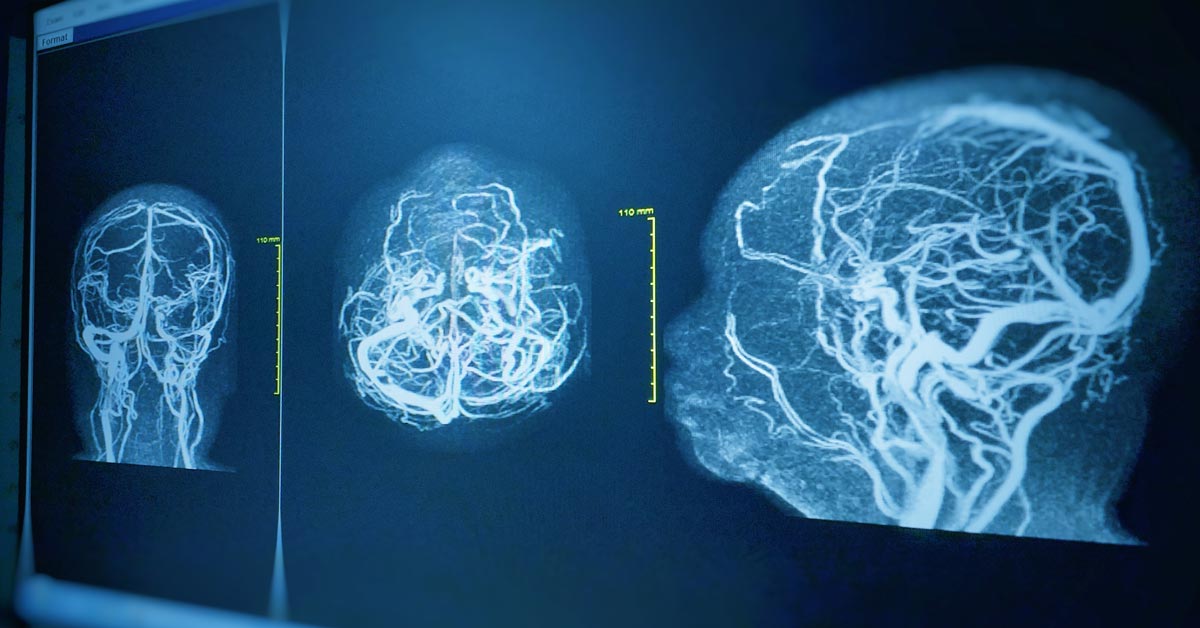

4. MRI หลอดเลือด (MR Angiography : MRA)

เป็นการตรวจหลอดเลือดโดยไม่ต้องฉีดสีในบางกรณี และไม่ใช้รังสี เช่น- หลอดเลือดสมองตีบหรือโป่งพอง

- ความผิดปกติของหลอดเลือดบริเวณคอ

- หลอดเลือดส่วนต่างๆ ของร่างกาย เช่น แขน ขา ช่องท้อง